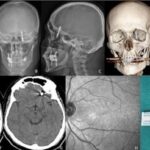

Nilüfer ilçesindeki özel bir diş kliniği, Yılmaz’a dişlerinin sallandığını söyleyerek implant önerdi. Doktor A.D.’nin uyguladığı işlem sırasında, implant vidası çene kemiğini delmek suretiyle kafatasına saplandı. Yılmaz, yaşadığı baygınlık sonrasında kliniğin aracıyla hastaneye kaldırılarak tomografi çektirildi. Çekim sonuçları, vidanın beynine kadar ilerlediğini gösterdi. Acilen ameliyata alınan Yılmaz, gerçekleştirilen zor bir operasyonla hayata döndürüldü.